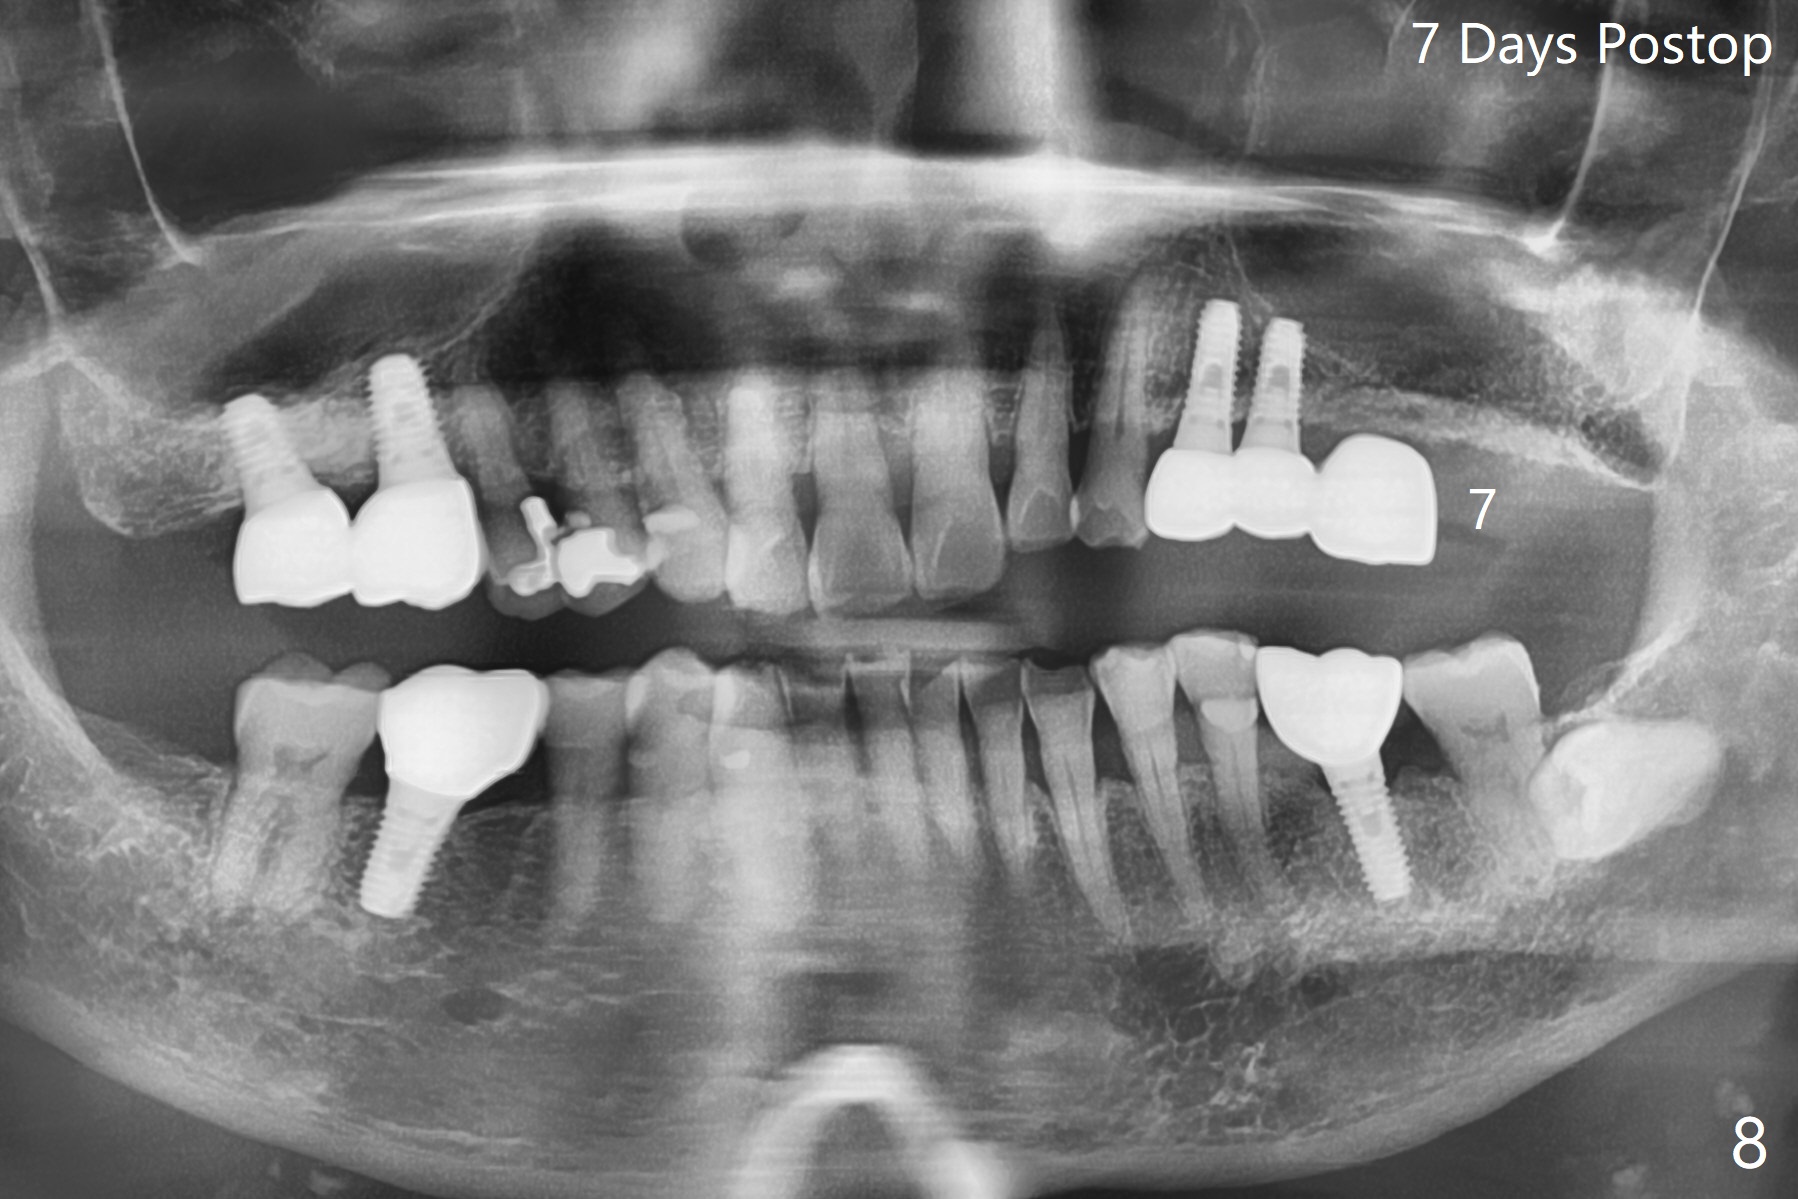

86岁男左上7折裂(图一),要求拔除,经过讨论(7拔除后,4-6悬臂桥可能断裂,对植体产生创伤,图二(左下7存在)),同意植骨。拔牙时发现中隔特别粗大(图三,五:S),三个牙槽窝根尖好像在中隔下面相互交通,擤鼻涕却没有气泡,仿佛与上颌窦没有相通。艰难清创后,放置Vanilla骨粉(图三),腭侧根特别容易填满,而颊侧根填入许多骨粉,术后CT远中颊侧骨粉尤其多(图四),上颌窦粘膜增厚(原来有季节性过敏)。术前根尖片显示远中颊侧根尖周围阴影很长(图五,六(虚线))。第二天早上鼻出血(仅有一次),今后牙槽窝明显比牙根长,清创控制深度,先放置胶原塞或PRF膜,后放骨粉。病人已经购买水牙线。术后7天树脂敷料稳定,局部卫生好(图七),骨粉好像进入上颌窦后部(图八)。术后1.5个月树脂敷料仍在原位,很容易撤除,牙槽窝愈合(图九),骨粉好像没有丢失(图十)。